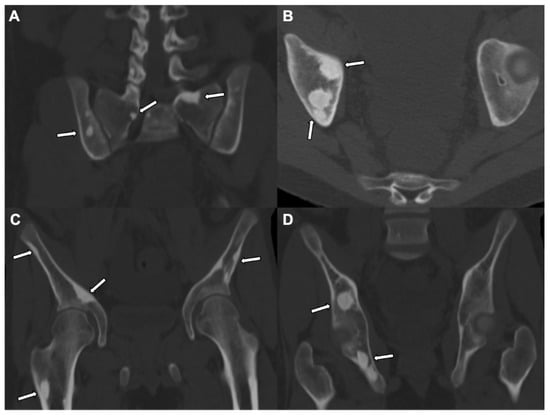

5. Osteoid Osteoma

| Radiographic/CT features | Juxtacortical, well-circumscribed homogenous sclerotic lesion | Homogenous intra-medullary sclerotic focus with spiculated margins | Small (less than 2 cm) cortical lucency with extensive surrounding sclerosis | Expansile large (more than 2 cm) lucent lesion with matrix mineralization |